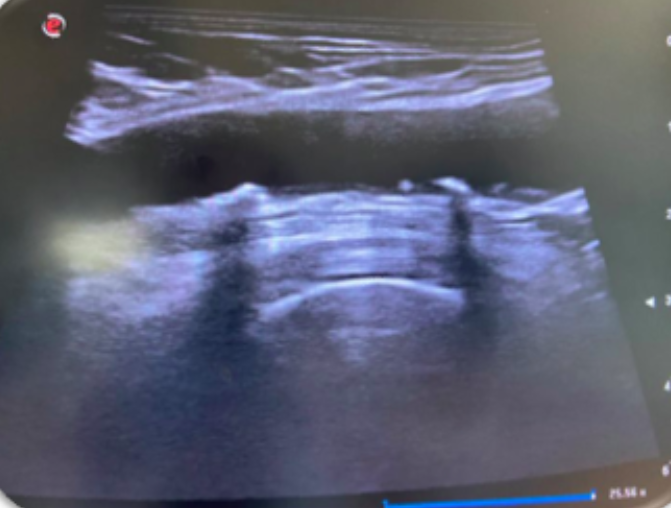

Los estudios de morbimortalidad reflejan que la enfermedad cardiovascular ocurre en más del 50% en varones y un 80% en mujeres catalogados de RCV bajo o moderado. En estudios sobre IAM el 50% de ellos presentaban uno o ningún FRCV. Así, podemos decir que existe un debate abierto sobre si las guías actuales infraestiman la arterioesclerosis ya existente, por lo que nos planteamos esta experiencia con la exploración ecográfica. Para ello realizamos una rotación en una unidad de RCV hospitalaria, con un protocolo específico para luego aplicarlo en el Centro de Salud. La valoración es similar a la utilizada en el Estudio PESA, donde se evalúa la existencia de placas de ateroma a nivel femoral, carotídeo, además de despistaje de aneurisma de aorta abdominal.

La ecografía es útil para valorar la arterioesclerosis mediante la detección de placa de ateroma en arterias carótidas y/o arterias femorales, indicando lesión de órgano diana (LOD) y llevándonos a facilitar la decisión de intensificar el tratamiento y así poder modificar la progresión de la enfermedad.

Implementar la ecografía clínica en la consulta del médico de familia para conseguir una valoración más precisa del RCV, mediante la detección de placa de ateroma y aneurisma de aorta abdominal, mejorando la atención y la valoración del RCV de nuestros pacientes ofertando la ecografía de forma protocolizada. Además de concienciar a la población sobre su patología, la necesidad de una prevención precoz y así poder frenar su progresión.